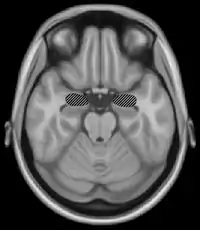

The basal ganglia are a group of nuclei which are located in the medial temporal lobe, above the thalamus and connected to the cerebral cortex. Specifically, the basal ganglia includes the subthalamic nucleus, substantia nigra, the globus pallidus, the ventral striatum and the dorsal striatum, which consists of the putamen and the caudate nucleus.[8] The basic functions of these nuclei deal with cognition, learning, and motor control and activities. The basal ganglia are also associated with learning, memory, and unconscious memory processes, such as motor skills and implicit memory.[4] Particularly, one division within the ventral striatum, the nucleus accumbens core, is involved in the consolidation, retrieval and reconsolidation of drug memory.[9]